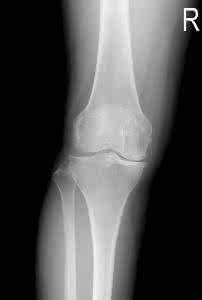

2009年04月01日15:57退行性关节炎是一种常见的关节疾病。在中国退行性关节炎患者往往只注重药物治疗以缓解疼痛,而忽视对病患关节的日常康复在骨性节炎治疗中的重要作用。下面就简单地向大家介绍一下日常关节康复注意事项吧:物理按摩

创伤性关节炎又称外伤性关节炎、损伤性骨关节炎,它是由创伤引起的以关节软骨的退化变性和继发的软骨增生、骨化为主要病理变化以关节疼痛、活动功能障碍为主要临床表现的一种疾病。任何年龄组均可发病,但以青壮年多见,多发于创伤后、承